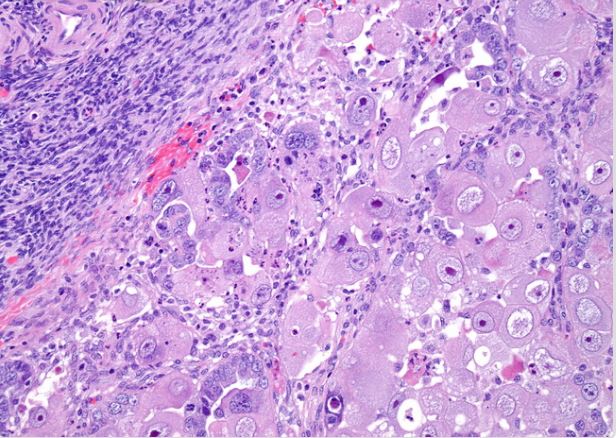

We consider two binary histopathology classification tasks, both framed as “cancer” vs. “non cancer”. The first dataset is the Ovarian Cancer & Subtypes Histopathology dataset111https://www.kaggle.com/datasets/bitsnpieces/ovarian-cancer-and-subtypes-dataset-histopathology, which contains digital pathology patches extracted from hematoxylin and eosin (H&E) stained ovarian tissue slides. We group the available subtypes into a single positive class (ovarian cancer) and use benign or non tumoral tissue as the negative class.

The second dataset is a subset of the LC25000 dataset222https://www.kaggle.com/andrewmvd/lung-and-colon-cancer-histopathological-images, which contains colon histopathology images with normal and tumoral samples. We select only colon images and map them to a binary label (cancer vs. non cancer). Representative examples of ovarian and colon patches for both classes (Figure 2).

| (a) Ovarian cancer | ||

| (b) Ovarian normal | ||

| (c) Colon cancer | ||

| (d) Colon normal | ||